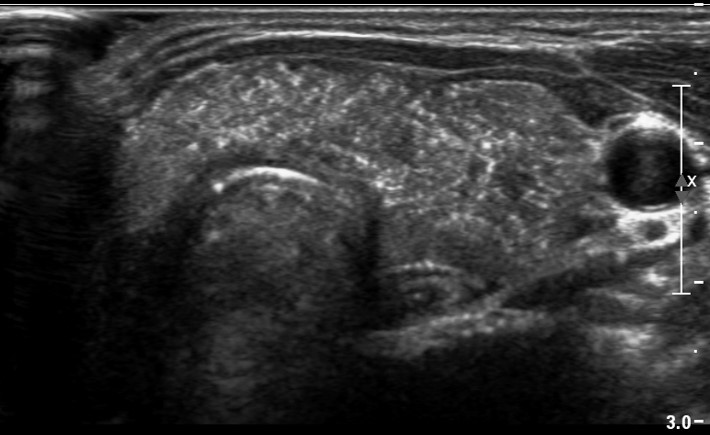

[353,] 42/F,검강검진상 발견된 갑상선 병변

Modality

US,CT,

Sae Rom Chung

,2025-10-25

진단은?

[Diagnosis]

Diffuse sclerosing subtype of PTC